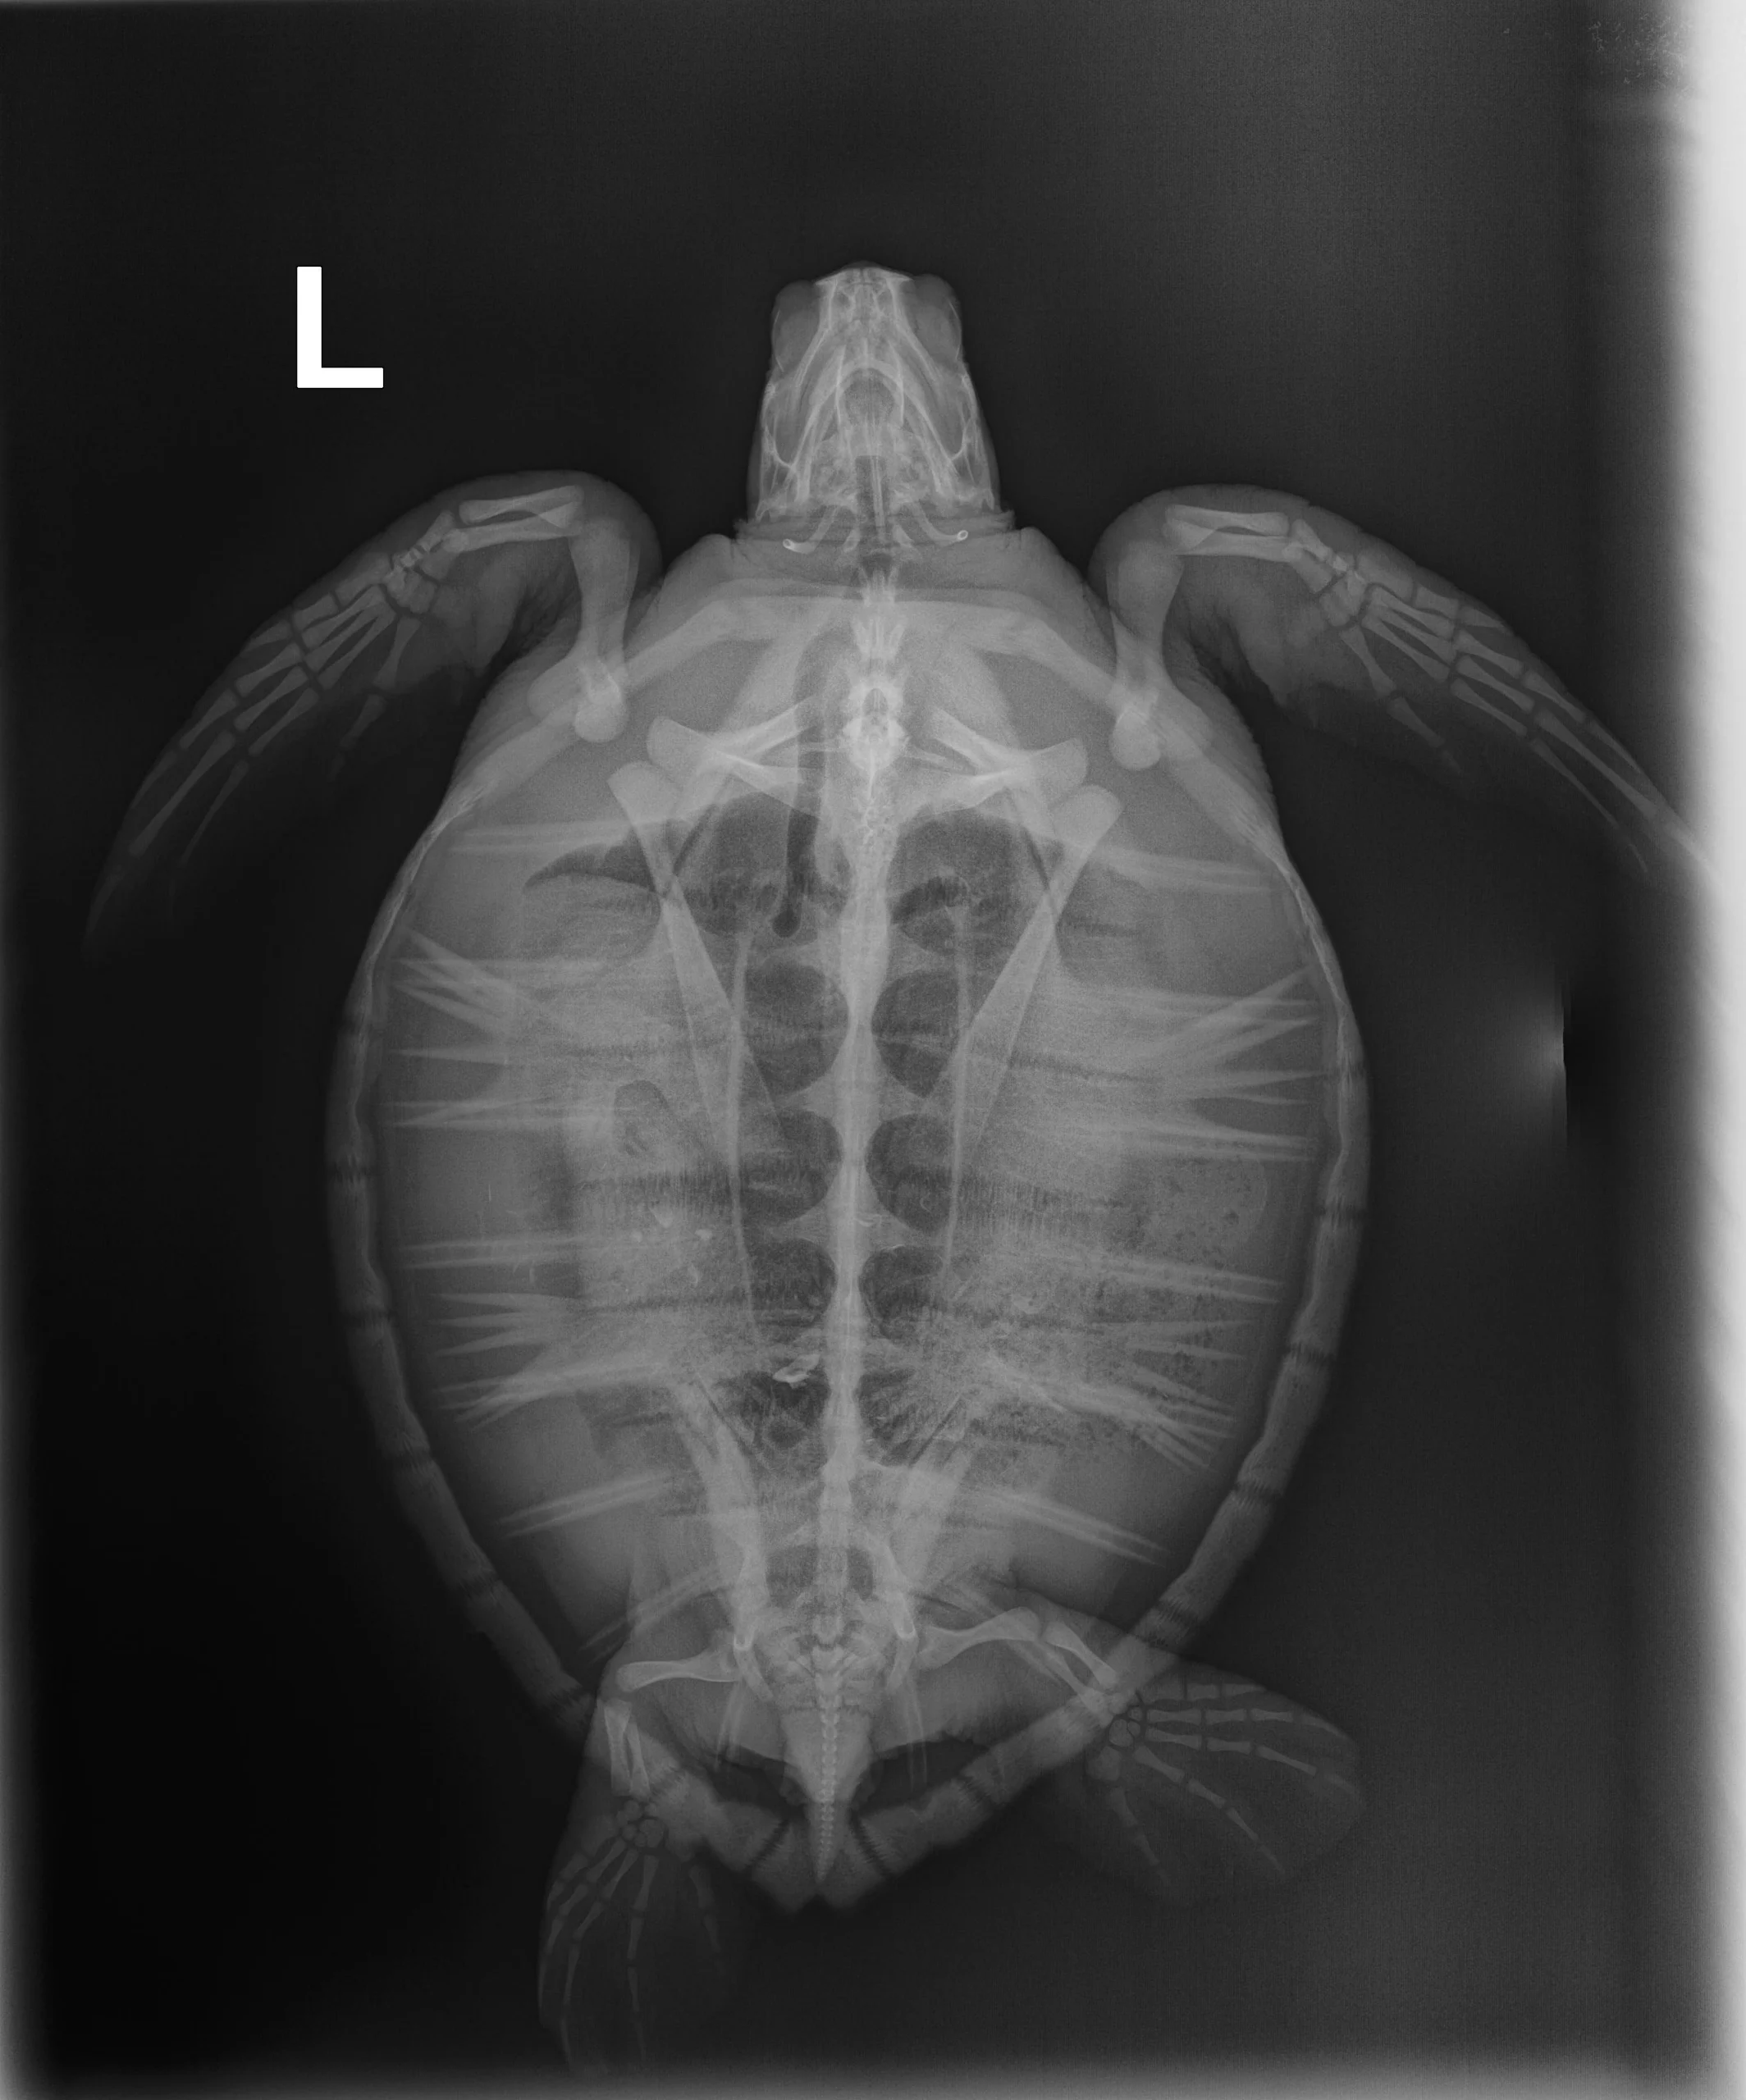

2.10 kg juvenile Atlantic Green sea turtle

External Carapace Notes: A few scrapes on the carapace

In House PCV: 33%, TS: 4 , Glucose: 201